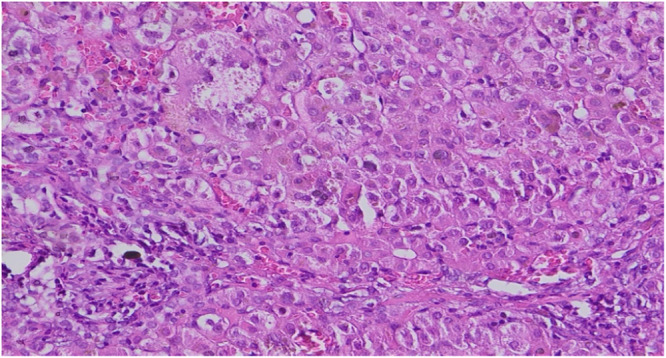

最近发现的一种与ZFYVE19基因突变有关的非综合征表型,其特征是出现胆汁淤积,并伴随婴儿期或幼儿期血清γ -谷氨酰转肽酶(GGT)升高。受影响的个体通常表现为肝脾肿大,并可能发展为门脉高压。该病被认为是胆管细胞特异性纤毛功能障碍的结果,表明纤毛病似乎仅限于肝脏。在这里,我们描述了一个一级近亲父母所生婴儿的病例,其中新生儿胆汁淤积伴随着GGT升高导致ZFYVE19缺乏症的发现。诊断是在对完整的外显子组测序进行深入分析后确定的。

A recent nonsyndromic phenotype, newly linked to mutations in the ZFYVE19 gene, is characterized by the appearance of cholestasis accompanied by an increase in serum gamma-glutamyltranspeptidase (GGT) from infancy or early childhood. Affected individuals generally present with hepatosplenomegaly and may develop portal hypertension. The disease is thought to be the result of cholangiocyte-specific ciliary dysfunction, indicating a ciliopathy that appears to be limited to the liver. Here, we describe the case of an infant born to first-degree consanguineous parents, in whom neonatal cholestasis accompanied by elevated GGT led to the discovery of a ZFYVE19 deficiency. The diagnosis was established following an in-depth analysis of the complete exome sequencing.